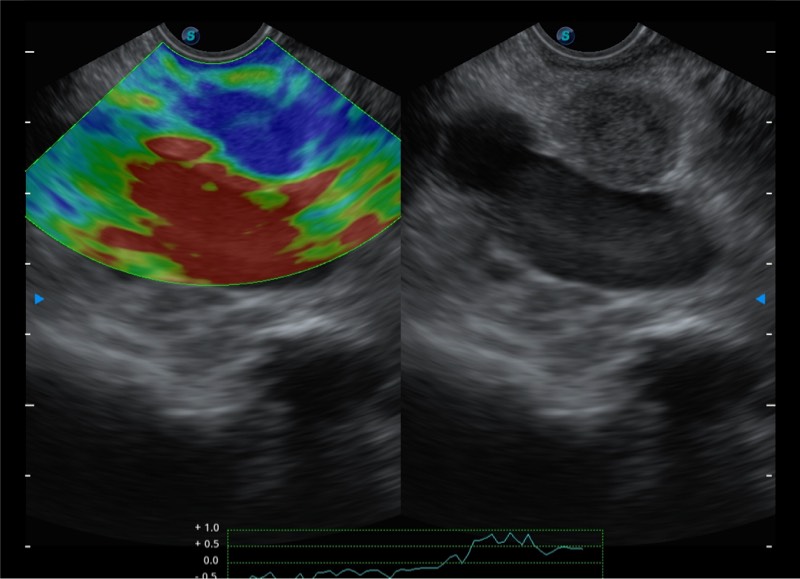

基于二十年的超声技术积累,银河集团官网提供了最新一代的独立超声主机,在提供高质量图像的同时满足多学科使用。具备常见多普勒技术并提供弹性成像、声学造影等高端影像技术。新一代传感器具有更强的抗干扰能力并减少图像伪影。

4-12MHZ宽频输出